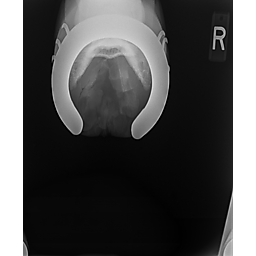

**Tex sells at the Colorado Horse Sale's Best of the West Select Sale on May 30th in Castle Rock, CO - He will complete the riding & handling Sift Exam, baseline veterinary exam, and will sell with 4 total radiographs (DLPMO & Front Foot Lateral)**